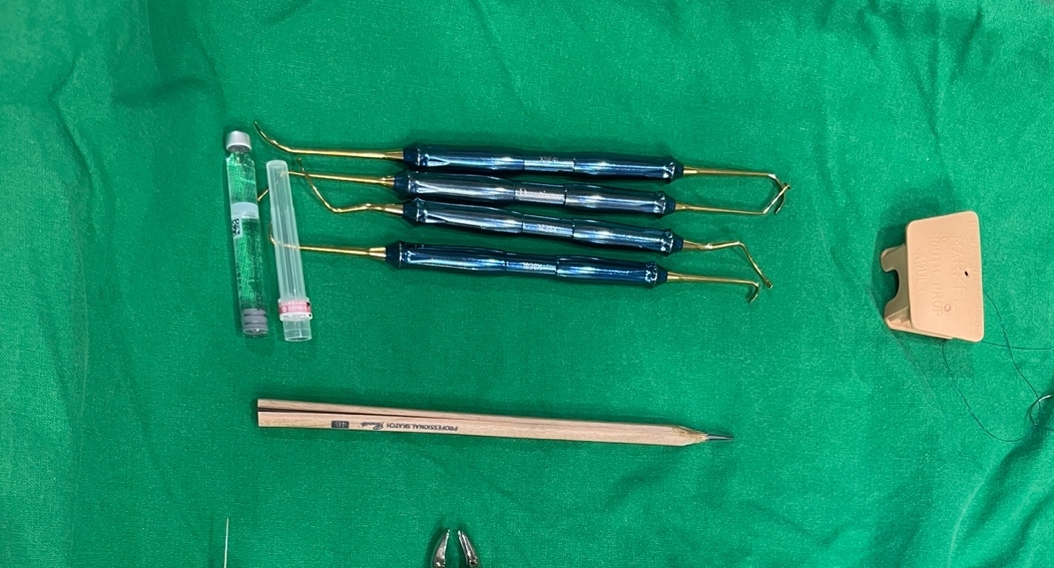

최소의 시간을 위하여 미리 스터디와 모의 수술로 수술을 시뮬래이션 해보았습니다. 대략 1시간이 나왔지만 실제로는 53분 정도에 전악식립과 상악동 거상술 시행, 지대주 연결 후 봉합까지 마무리 되었습니다. 이젠 수술팀이 어느 정도 괘도에 오른것 같습니다. 제 1조수와 보조하는 2조수가 술식을 다 파악해서 준비부터 마무리까지 계속 시간이 줄어들고 있습니다.